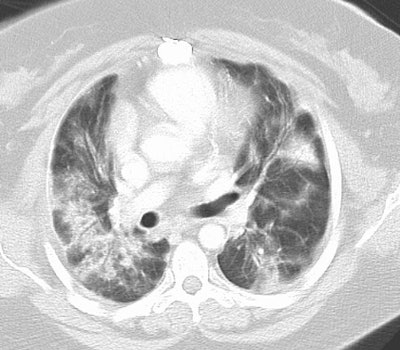

Cryptogenic Organizing Pneumonia (BOOP):

The patient shown below had a long history of inflammatory bowel disease for which she was receiving treatment with sulfasalazine. This agent can result in BOOP.

The CT scan demonstrates subpleural, patchy consolidations with air bronchograms. Patchy areas of ground-glass are also seen. Peribronchial thickening as shown in this case is a common finding.